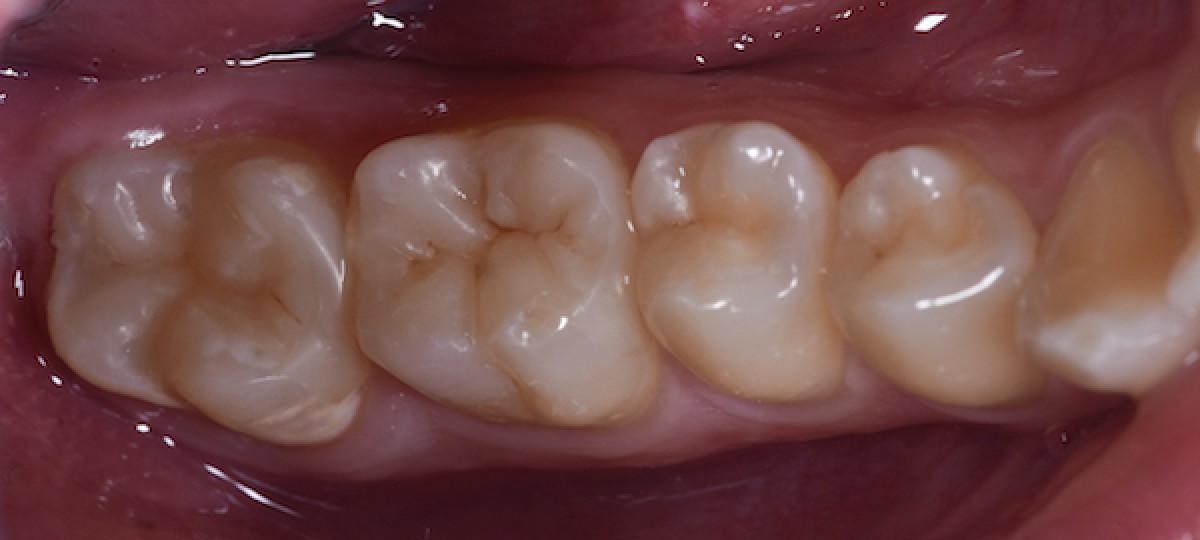

Four months follow-up (Fig.15)